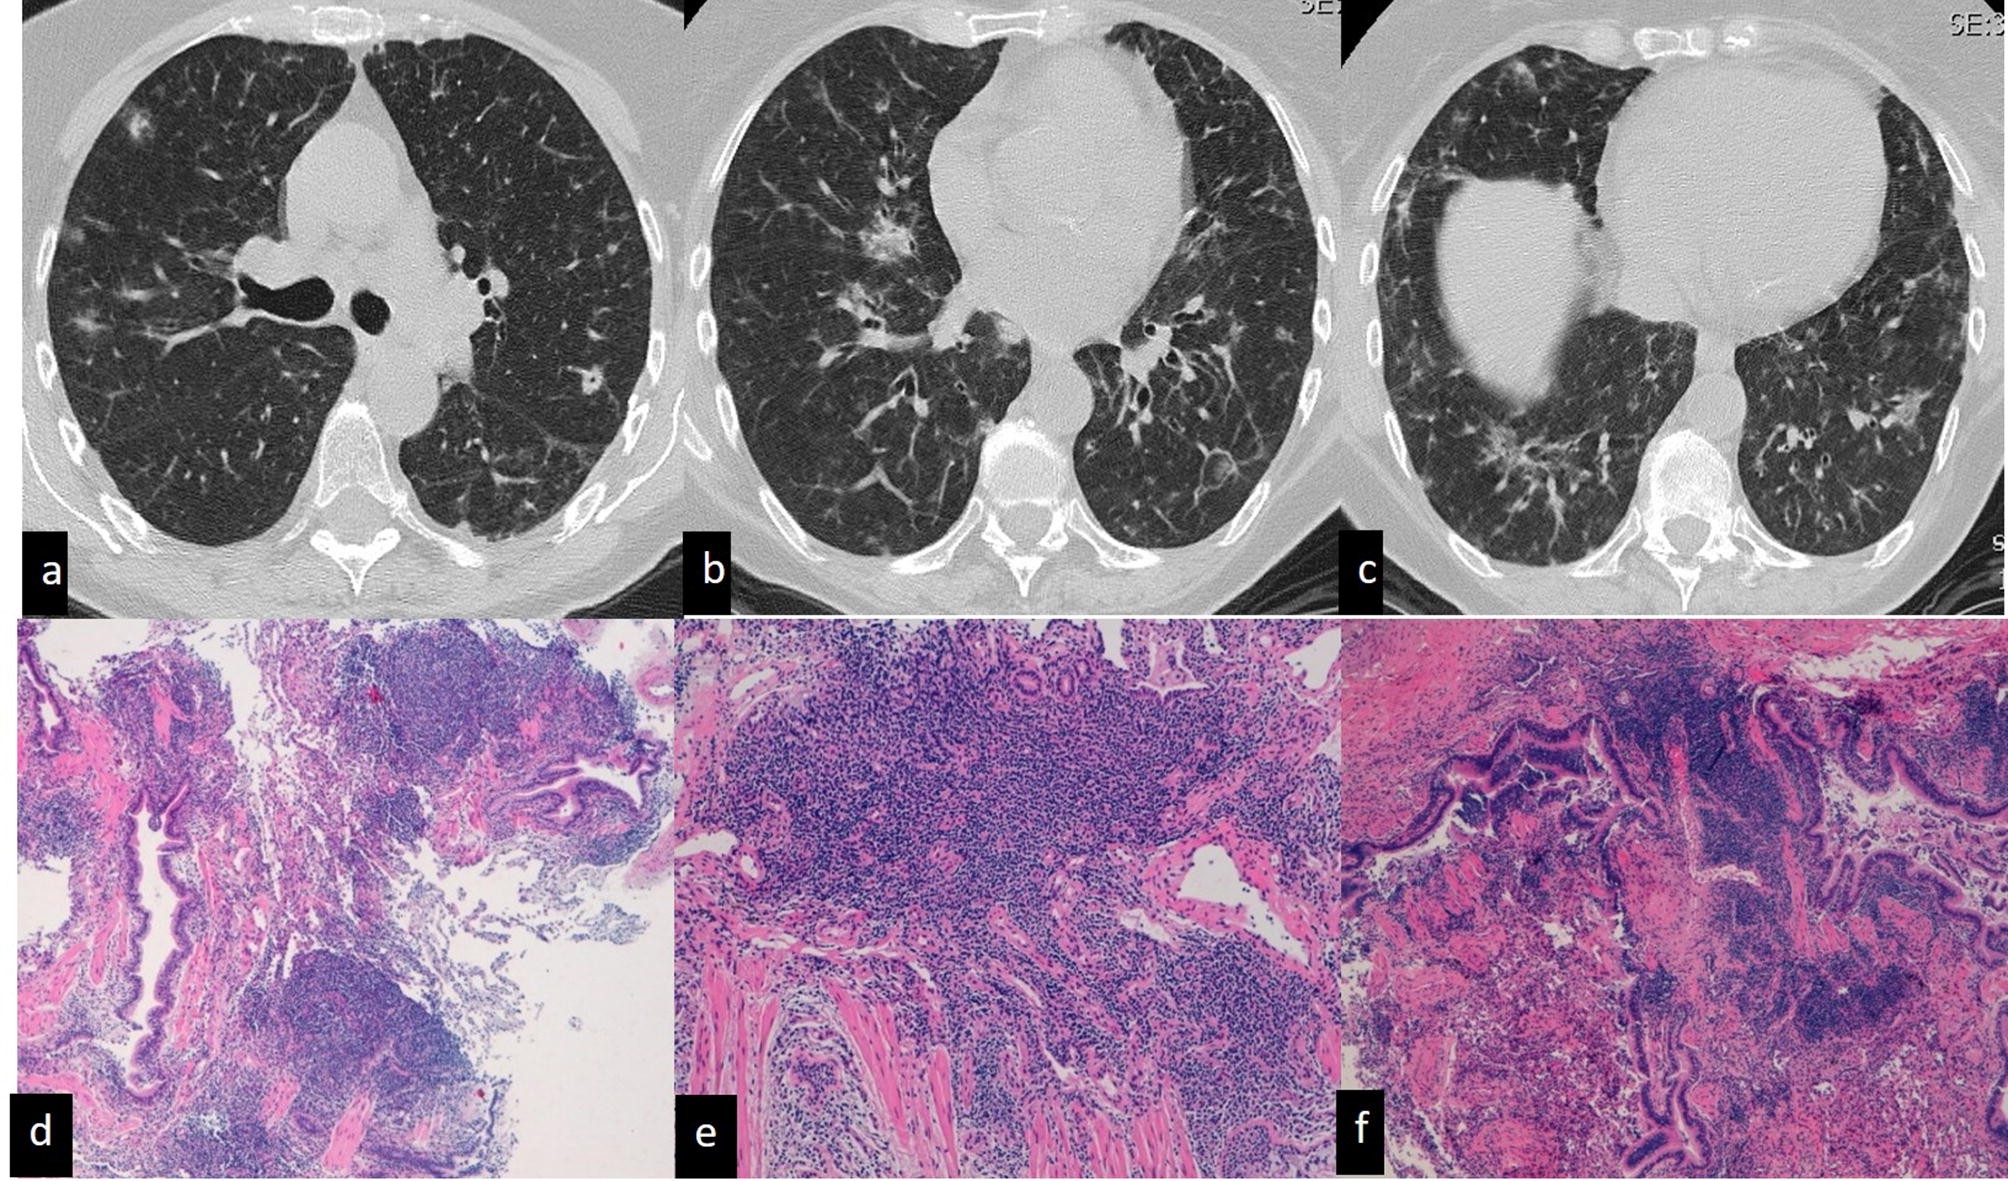

To improve the long-term survival of patients with ARS-ILD novel therapies beyond CS and IS that can prevent refractory fibrosis progression and AE development are required. Respiratory bronchiolitis associated interstitial lung disease RB-ILD is a recently described clinicopathological entity that occurs almost exclusively in current heavy cigarette smokers. And include in order of frequency central bronchial wall thickening 90 peripheral bronchial wall thickening 86 centrilobular.

The clinical and physiologic features of respiratory bronchiolitis RB-interstitial lung disease ILD have been previously described. In a subset of patients however this is the only pathologic finding and seems to account for clinical interstitial lung disease.

It is a form of idiopathic interstitial pneumonia associated with smoking. The clinical and physiologic features of respiratory bronchiolitis RB-interstitial lung disease ILD have been previously described. In a subset of patients however this is the only pathologic finding and seems to account for clinical interstitial lung disease. Few cases have been reported in the literature and no studies have been carried out on the effect of treatment which currently consists of smoking cessation with or without corticosteroids. Respiratory bronchiolitis refers to a histological finding that can be often seen in heavy smokers. Symptoms include cough and breathlessness during exertion. The concept of RBILD has changed over time with the recognition that histologically and radiologically RB and RBILD are usually indistinguishable. Portnoy J Veraldi KL Schwarz MI Cool CD Curran-Everett D Cherniack RM King TE Brown KK. Respiratory bronchiolitisassociated interstitial lung disease RBILD is a syndrome of small airway inflammation and interstitial lung disease occurring in smokers.

The long-term outcome of interstitial lung disease with anti-aminoacyl-tRNA synthetase antibodies The long-term outcome of ARS-ILD was significantly better than that of IPF regardless of the presence or absence of myositis. Although the long-term survival of patients with ARS-ILD is better that of those with IPF ARS-ILD can be a progressive and fatal disease even with long-term IS therapies. It is a histological finding not a pathological description. A clinicopathologic study in current smokers ex-smokers and never-smokers. Symptoms include cough and breathlessness during exertion. And include in order of frequency central bronchial wall thickening 90 peripheral bronchial wall thickening 86 centrilobular. Respiratory bronchiolitis associated interstitial lung disease RB-ILD presenting with haemoptysis.